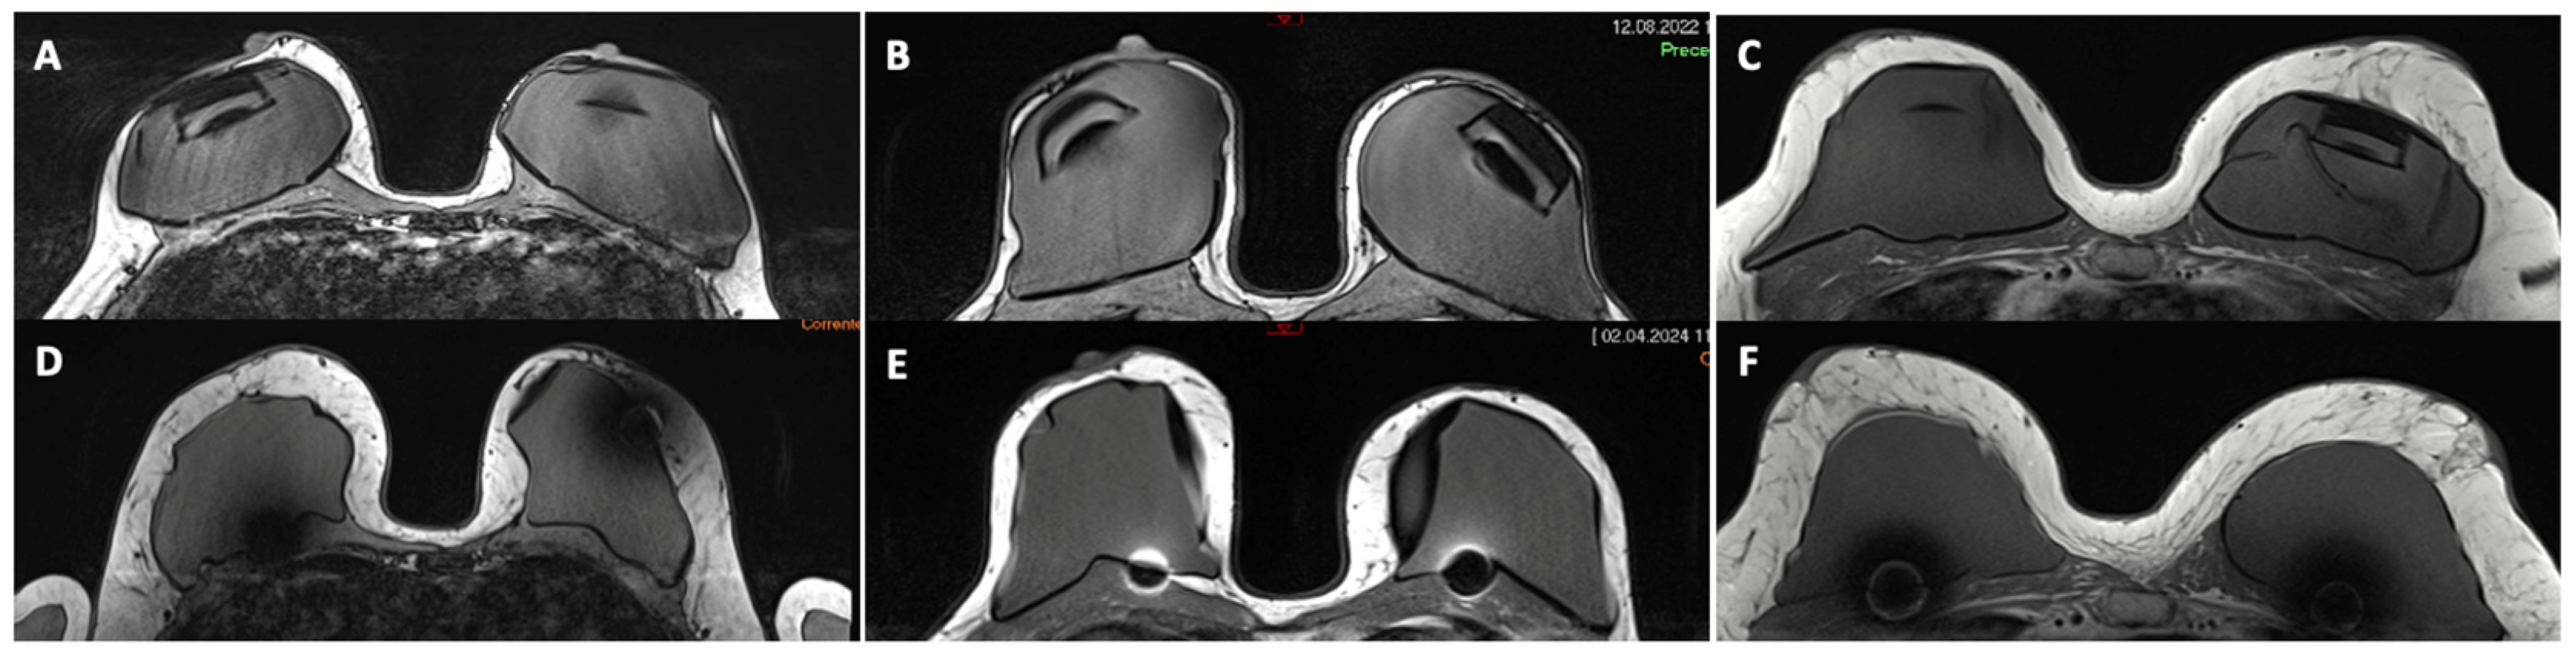

2.3. Measurement of Tissue Thickness